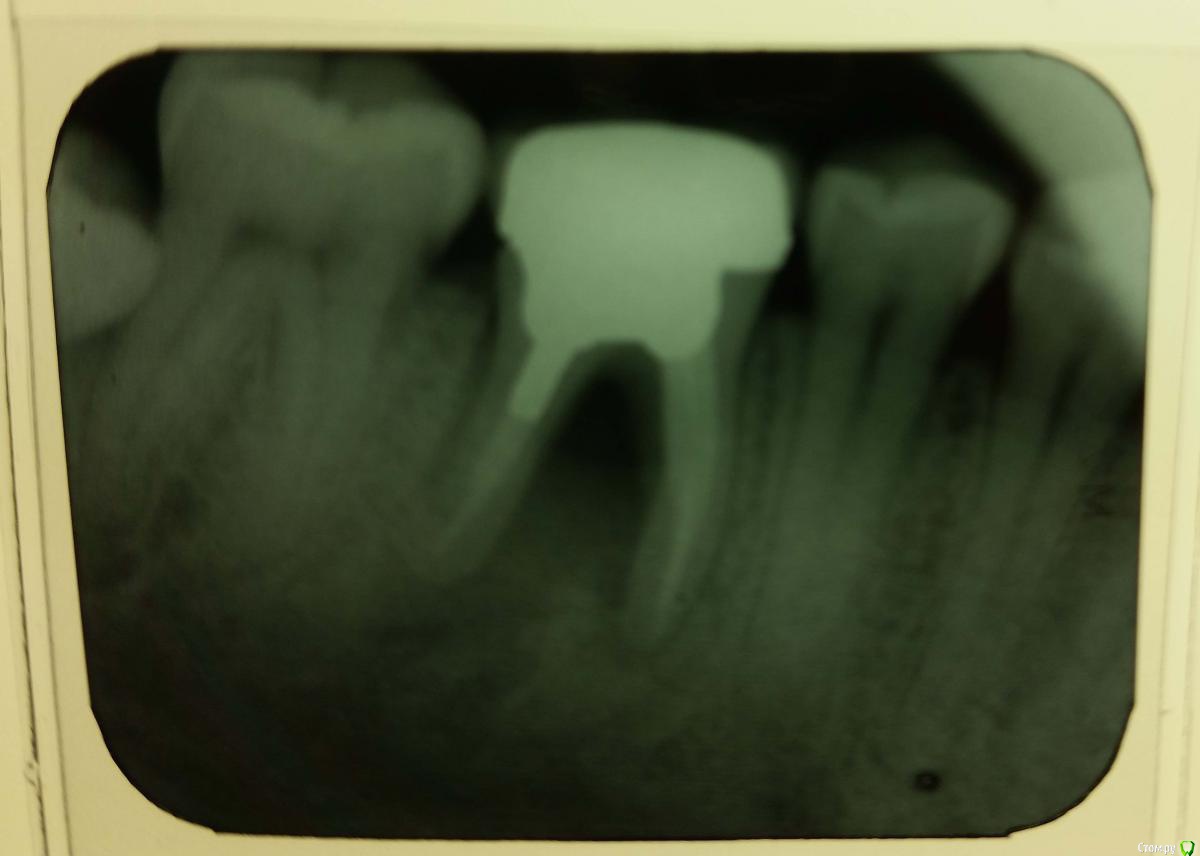

tanker Опубликовано 12 ноября, 2015 Поделиться Опубликовано 12 ноября, 2015 прошу советаистория:лет 7 назад поставили коронку на большой зуб нижний правый, из которого на тот момент давно выпала пломба или он вообще потрескался, плохо помнюспустя 4-5 лет внезапно в районе этой коронки стало иногда сильно болеть, но проходило за день-двав один из эпизодов я попал к дантисту, он сказал, что проблема в коронке, он их не лечит и предложил попробовать сначала антибиотики или удалитьболь прошла, пока я шёл покупать антибиотикис тех пор зуб болит редко и неподолгусейчас:нахожусь за границей, и нет возможности сходить к своему стоматологу. зуб не болит, но кажется, что он немного качается и иногда как бы немного выступает вверх. есть гнилой привкус во рту и иногда, кажется, кровь. есть ночной шум в правом ухе, но не уверен, что это связано. проблем с жеванием нет.сходил к новому дантисту на профилактику -- он сказал, что больших проблем нет, кроме этого зуба. при этом, сама по себе коронка и корни в порядке, но есть инфекция между корней. говорил, что видит выделения при нажатии на десну с внутренней стороны. сказал, что это нелегко вылечить и предложил удалить зуб и поставить имплант задорого, или (почему-то он склонялся к этому варианту) вырезать часть десны со внутренней стороны, чтобы, как я понял, во время чистки зубов дополнительно прочищать пространство между корнями с помощью спец мини щетки или шприца с искривлённой затуплённой иглой, которую он показывал. снимок зуба прилагаю. вопросы:1. как болезнь называется по-научному?2. делать имплант или резать десну?3. если делать имплант, лучше делать сразу когда зуб удаляют, или можно (и нужно?) подождать?Спасибо! Ссылка на комментарий